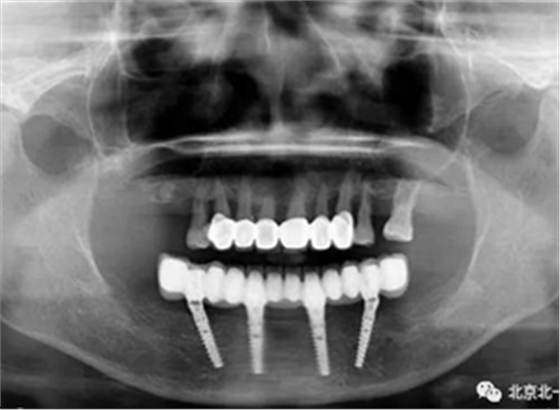

圖十五:術(shù)后即刻拍X片

圖二十一:半年后復(fù)查X片